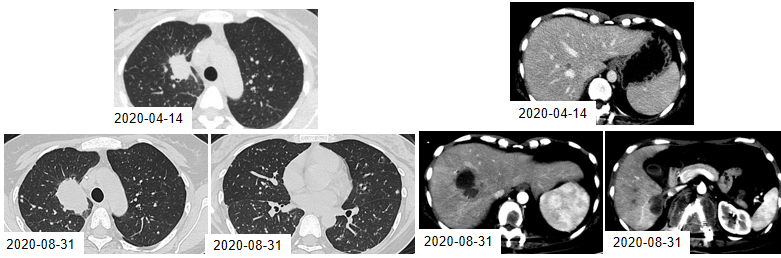

图4. 2019年11月18日与2020年4月14日的CT检查结果

2020年8月31日,CT检查提示:肺部病灶、肝脏病灶均较前明显增大,考虑奥希替尼耐药,无进展生存期(PFS)为9.1个月。

图5. 2020年4月14日与8月31日的CT检查结果